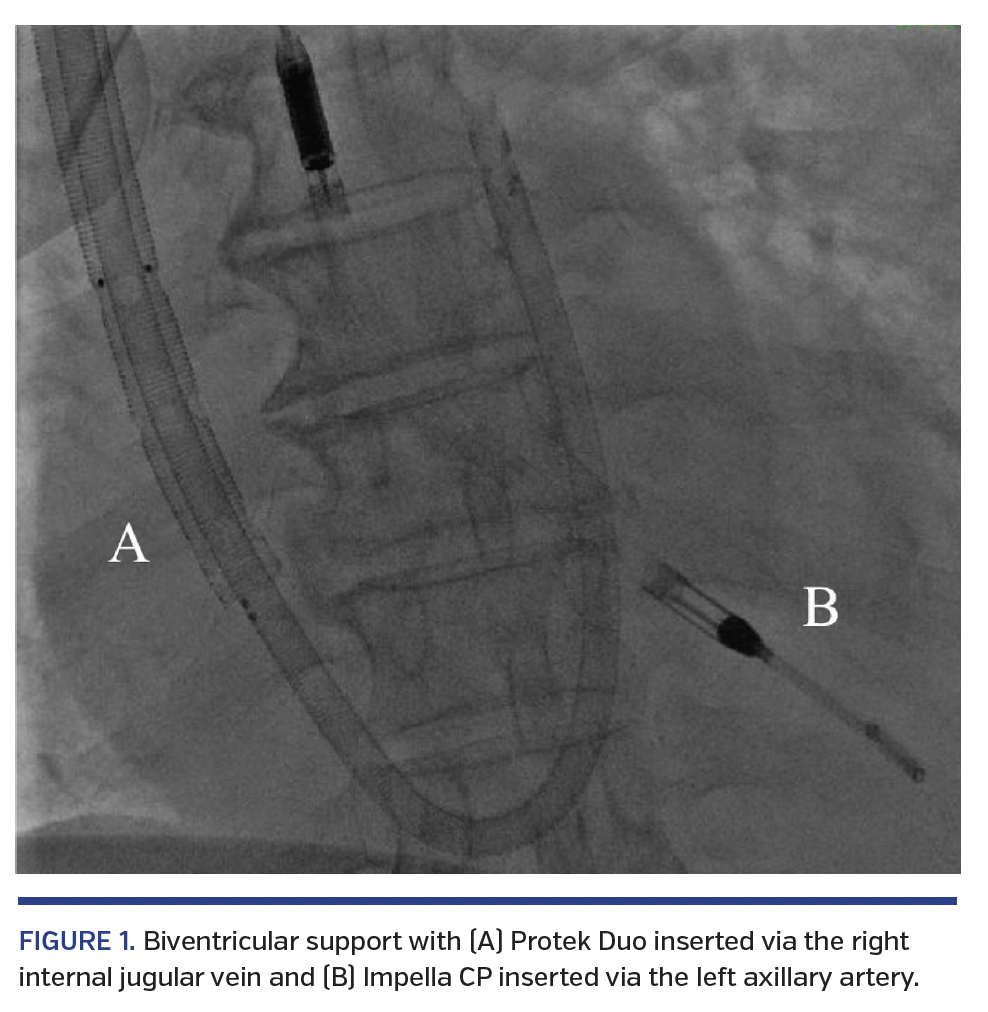

A 58-year-old female with no prior medical history presented with cardiogenic shock due to viral myocarditis. She had angiographically normal coronary arteries. Bedside echocardiogram showed global hypokinesis of the left ventricle (LV) with left ventricular ejection fraction (LVEF) of 10%. Right ventricular (RV) function was severely impaired. That patient needed biventricular mechanical circulatory support (MCS). Using moderate sedation, an Impella CP (Abiomed) was placed percutaneously through the left axillary artery. Subsequently, a Protek Duo device (LivaNova) was inserted into the right internal jugular (IJ) vein, positioned distally into the main pulmonary artery (PA), and connected to a TandemHeart pump (LivaNova) (Figure 1). The patient was able to ambulate with careful supervision. Biventricular support resulted in stable hemodynamics. The biventricular support devices were weaned and removed on hospital day 6. LVEF on discharge was 50%. To our knowledge, this is the first reported case of full biventricular MCS with the combination of Impella and Protek Duo. The Protek Duo is a dual-lumen cannula inserted via the right IJ vein, with its proximal inflow lumen positioned in the right atrium and distal lumen positioned in the main PA. These lumens are connected with the paracorporeal TandemHeart pump, which allows flow of up to 5 L/min. The alternative percutaneous option for RV support is the Impella RP (Abiomed), which must be placed in the femoral vein, preventing ambulation. The axillary and IJ vein positions for devices are probably less prone to infection compared with the femoral area. The combination of an Impella inserted via the axillary artery with the Protek Duo is a viable option, allowing ambulation while providing biventricular support.